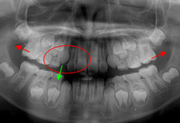

床矯正

平成20年9月20日

治療開始

平成21年4月25日

治療開始7ヶ月後

平成22年3月20日

治療開始18ヶ月後